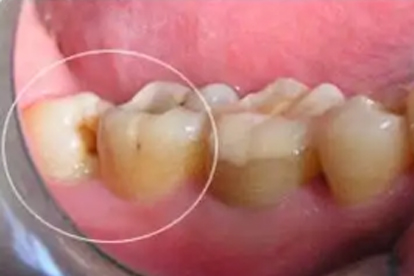

阻生智齿是导致邻牙移位的主要原因,通过手术拔除可消除挤压源。术前需拍摄口腔全景片评估智齿位置,埋伏阻生智齿需采用翻瓣去骨术,术后可能出现肿胀疼痛,可遵医嘱使用布洛芬缓释胶囊、头孢克洛分散片、复方氯己定含漱液等药物预防感染。拔牙后24小时内避免漱口和进食过热食物。

牙齿移位常伴随牙龈退缩和牙槽骨吸收,需加强牙周基础治疗。每日使用巴氏刷牙法配合牙线清洁,定期进行超声波洁治去除菌斑结石。出现牙周脓肿时可短期使用甲硝唑芬布芬胶囊,配合西吡氯铵含片抑制口腔细菌。